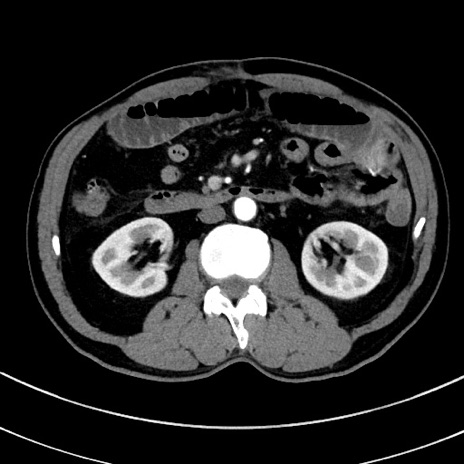

症例8(横断像)

【症例】 60歳代男性

【主訴】 黒色吐物

【現病歴】 4日前から嘔気自覚、2日前の朝食後にも嘔気あり、自分で手で嘔吐反射起こし嘔吐したところ血が混ざっていたため受診。

【既往歴】 5年前汎発性腹膜炎を伴う急性虫垂炎で手術、高血圧、前立腺肥大症、高脂血症

【身体所見】 腹部正中に手術癩痕あり 腹部平坦・軟圧痛なし膨満感あり

【データ】WBC 8400、CRP 4.54